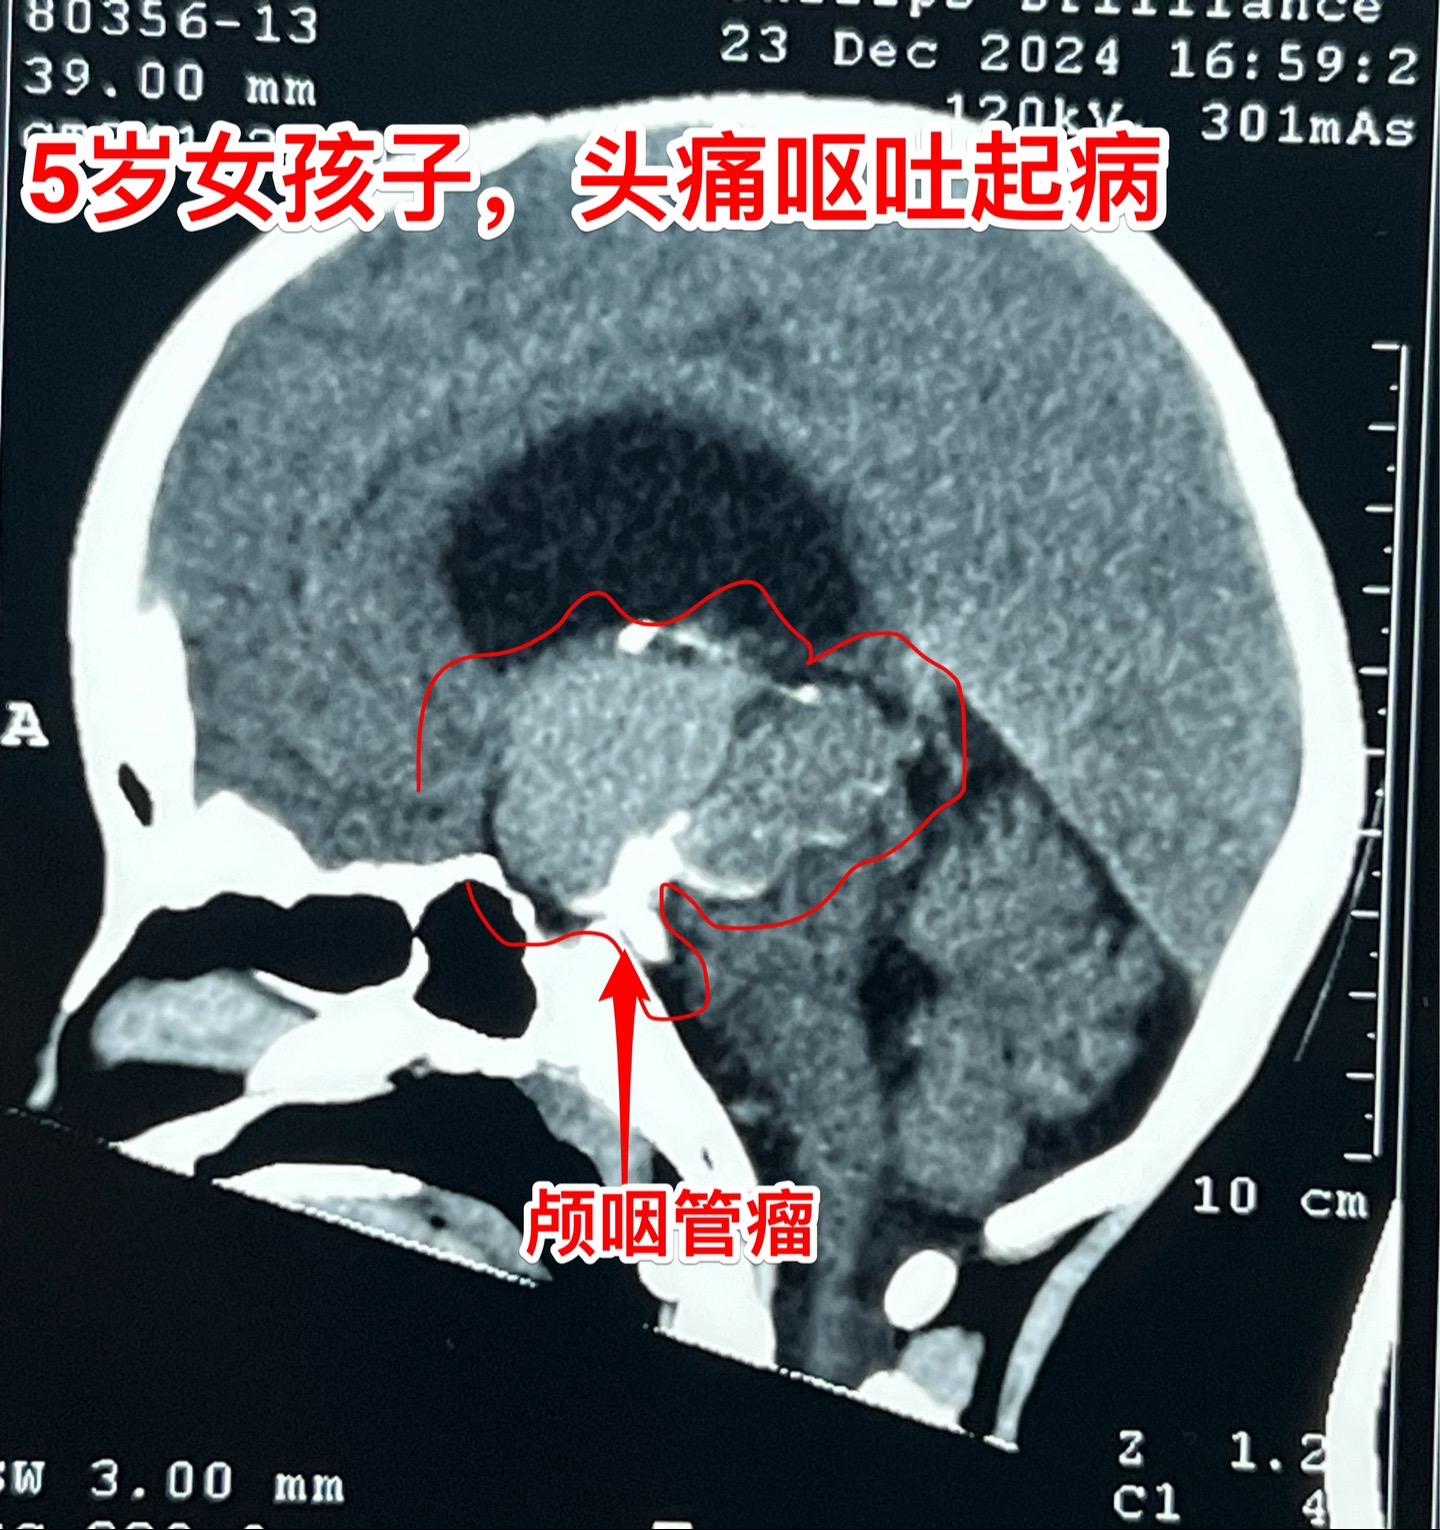

五岁商丘女孩颅咽管瘤像鸡蛋大。女孩子因为反复头痛、呕吐起病,一开始怀疑是胃肠炎,治疗后效果不好。于2024年12月18日作脑部磁共振和CT发现脑部肿瘤,怀疑是颅咽管瘤,孩子的妈妈和我加了,说肿瘤像鸡蛋那么大,焦急万分。 小孩子几经周折,最终到三博脑科医院找我办理住院手续。刚刚住院后又患感冒,发烧、咳嗽。感冒治好之后才于2025月1月7日作了手术。手术很顺利。 这个肿瘤体积大,导致脑积水,主体位于第三脑室内。对于我们科来说,这样的手术还不算是最难的。 希望小